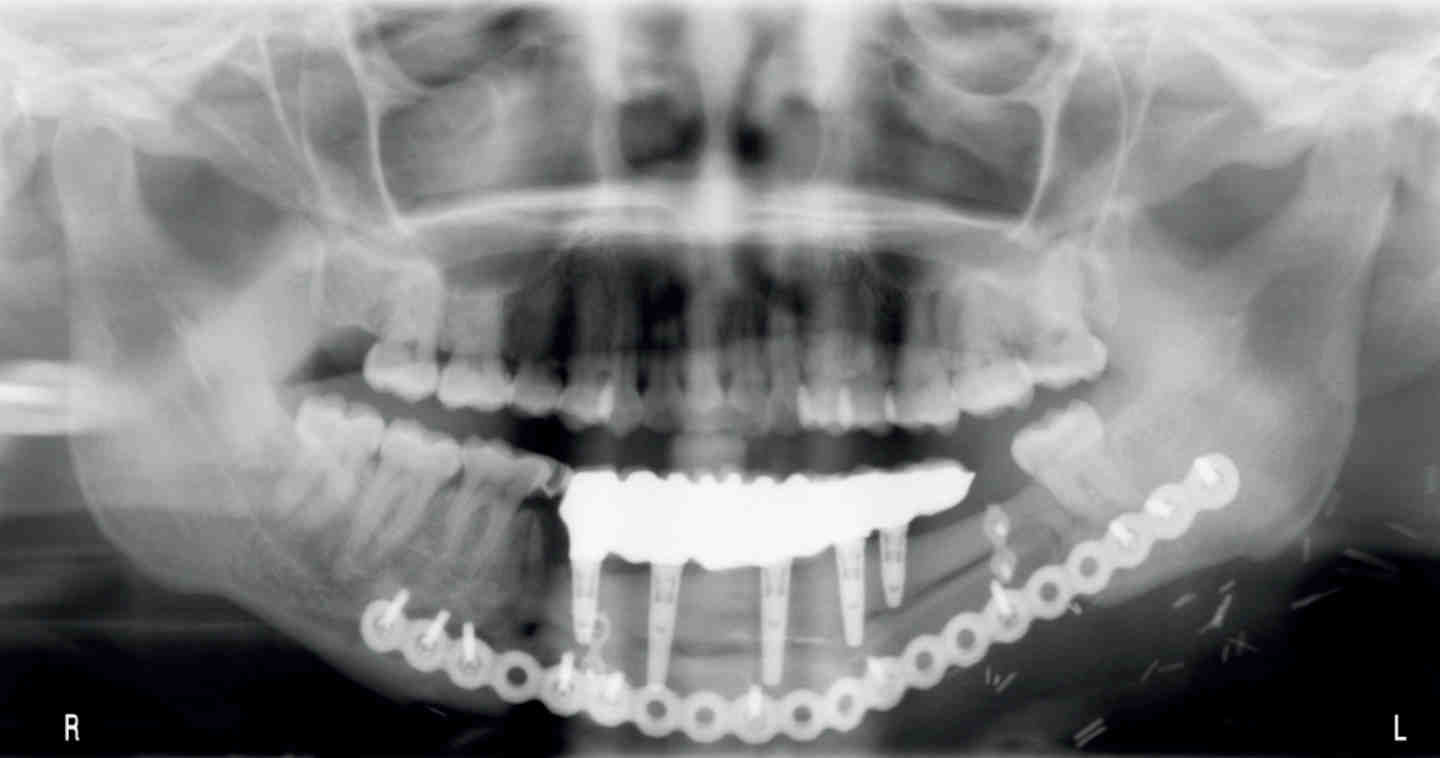

Getting a dental implant requires oral surgery and as a result a patient can be sedated. There are many types of anesthesia that could be used. Which one is chosen depends on factors such as the number of implants to be placed and the comfort and personal preferences of the patient.

Early implant placement involves placing the implant 2-3 months after extraction, during which time the bone heals and the site is better prepared. Early implants should be placed within this timeframe since two-thirds of bone resorption occurs within the first three months after extraction.

Do you have to be put to sleep to get dental implants?

Dental implants are surgically implanted into the jawbone. While surgeries can make a patient appear completely unconscious, dental implants are only a minor surgery. They do not require complete sedation for the treatment to be comfortable.